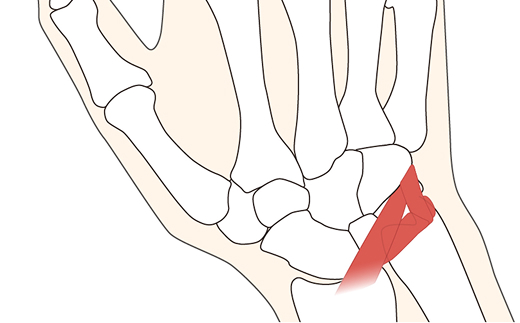

母指(親指)の根元にある母指CM関節の軟骨が摩耗するなど、亜脱臼状態(ズレたり、外れかかること)になると、「物をつかむ」「瓶のふたを開ける」「包丁で何かを切る」といった作業で母指に力のかかる動作で痛みを伴うようになります。これが母指CM関節症です。

40歳以上、特に閉経後の女性や、つまみ動作の多い職業の方が発症しやすいのが特徴です。また男性は、力仕事やけがによって発症するケースがよくみられます。

※赤丸内:関節軟骨は消失し、大きな骨棘が形成されています。

まずは装具装着などによる保存的な治療を行いますが、疼痛が改善しない場合は手術となります。 手術方法もさまざまですが、当院では、ミニタイトロープを用いた母指CM関節形成術や、自分の腱を用いた関節形成術を行っております。

※高強度の医療用ファイバーワイヤー(強靭な糸)で関節を制動する新しい術式です。

高度な施術の技能が必要となりますが、「つかむ力」や「可動域」を確保しつつ「早期に痛みをとる」など多くの点で低侵襲な術式といえます。

病状や年齢、リハビリテーションの実施内容など、個人差がありますので一概には言えませんが、実際に屈強な大工さんや宅配業者さんなど、力仕事をされる患者さんが、手術後におおよそ元のレベルにまで回復され、仕事へ復帰されています。

この術式を京都市内で行っているのは当院のほか、公的病院2施設だけ(2022年5月時点)で、全国的にも実施施設が少ない状況です。質問などございましたら、是非、当院の手外科センターまでお問い合わせください。